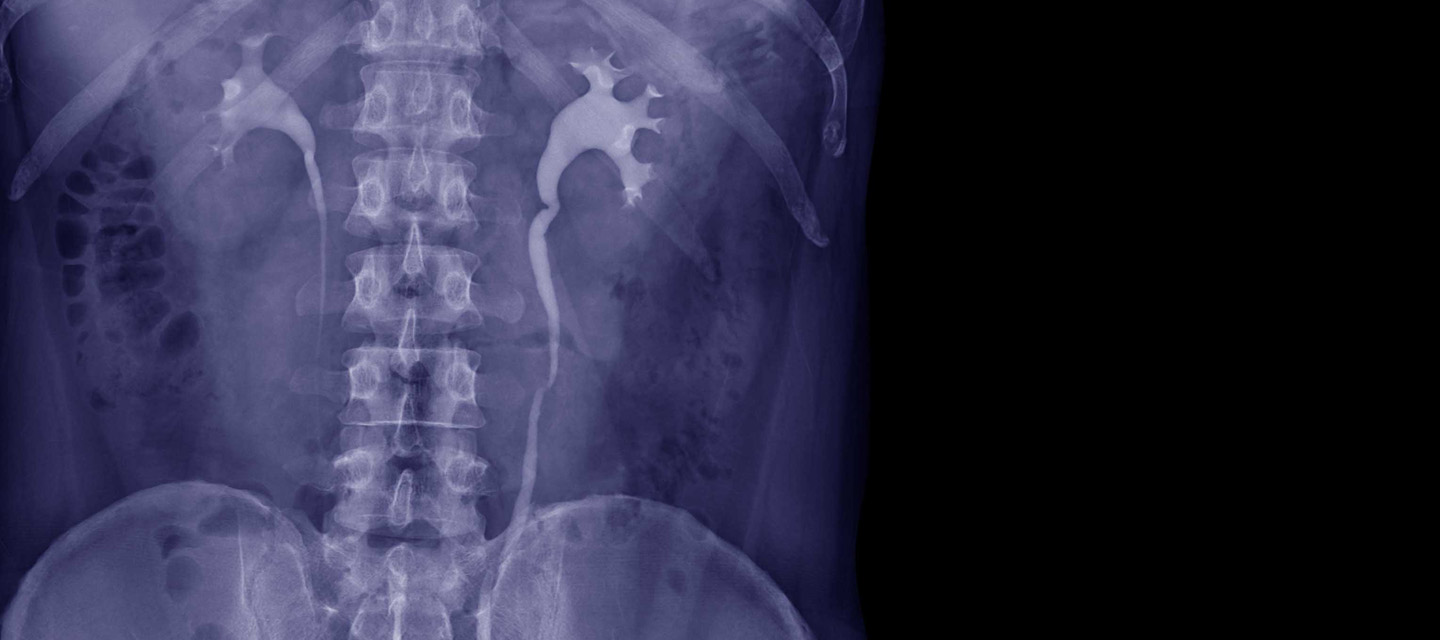

• التصوير الإشعاعي للصدر والبطن: مثل: الأشعة السينية للصدر ، الأشعة السينية للبطن في حالتي الوقوف والاستلقاء ، الأشعة السينية للكلى والحالب والمثانة